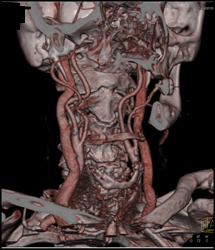

Carotid Artery Stenosis